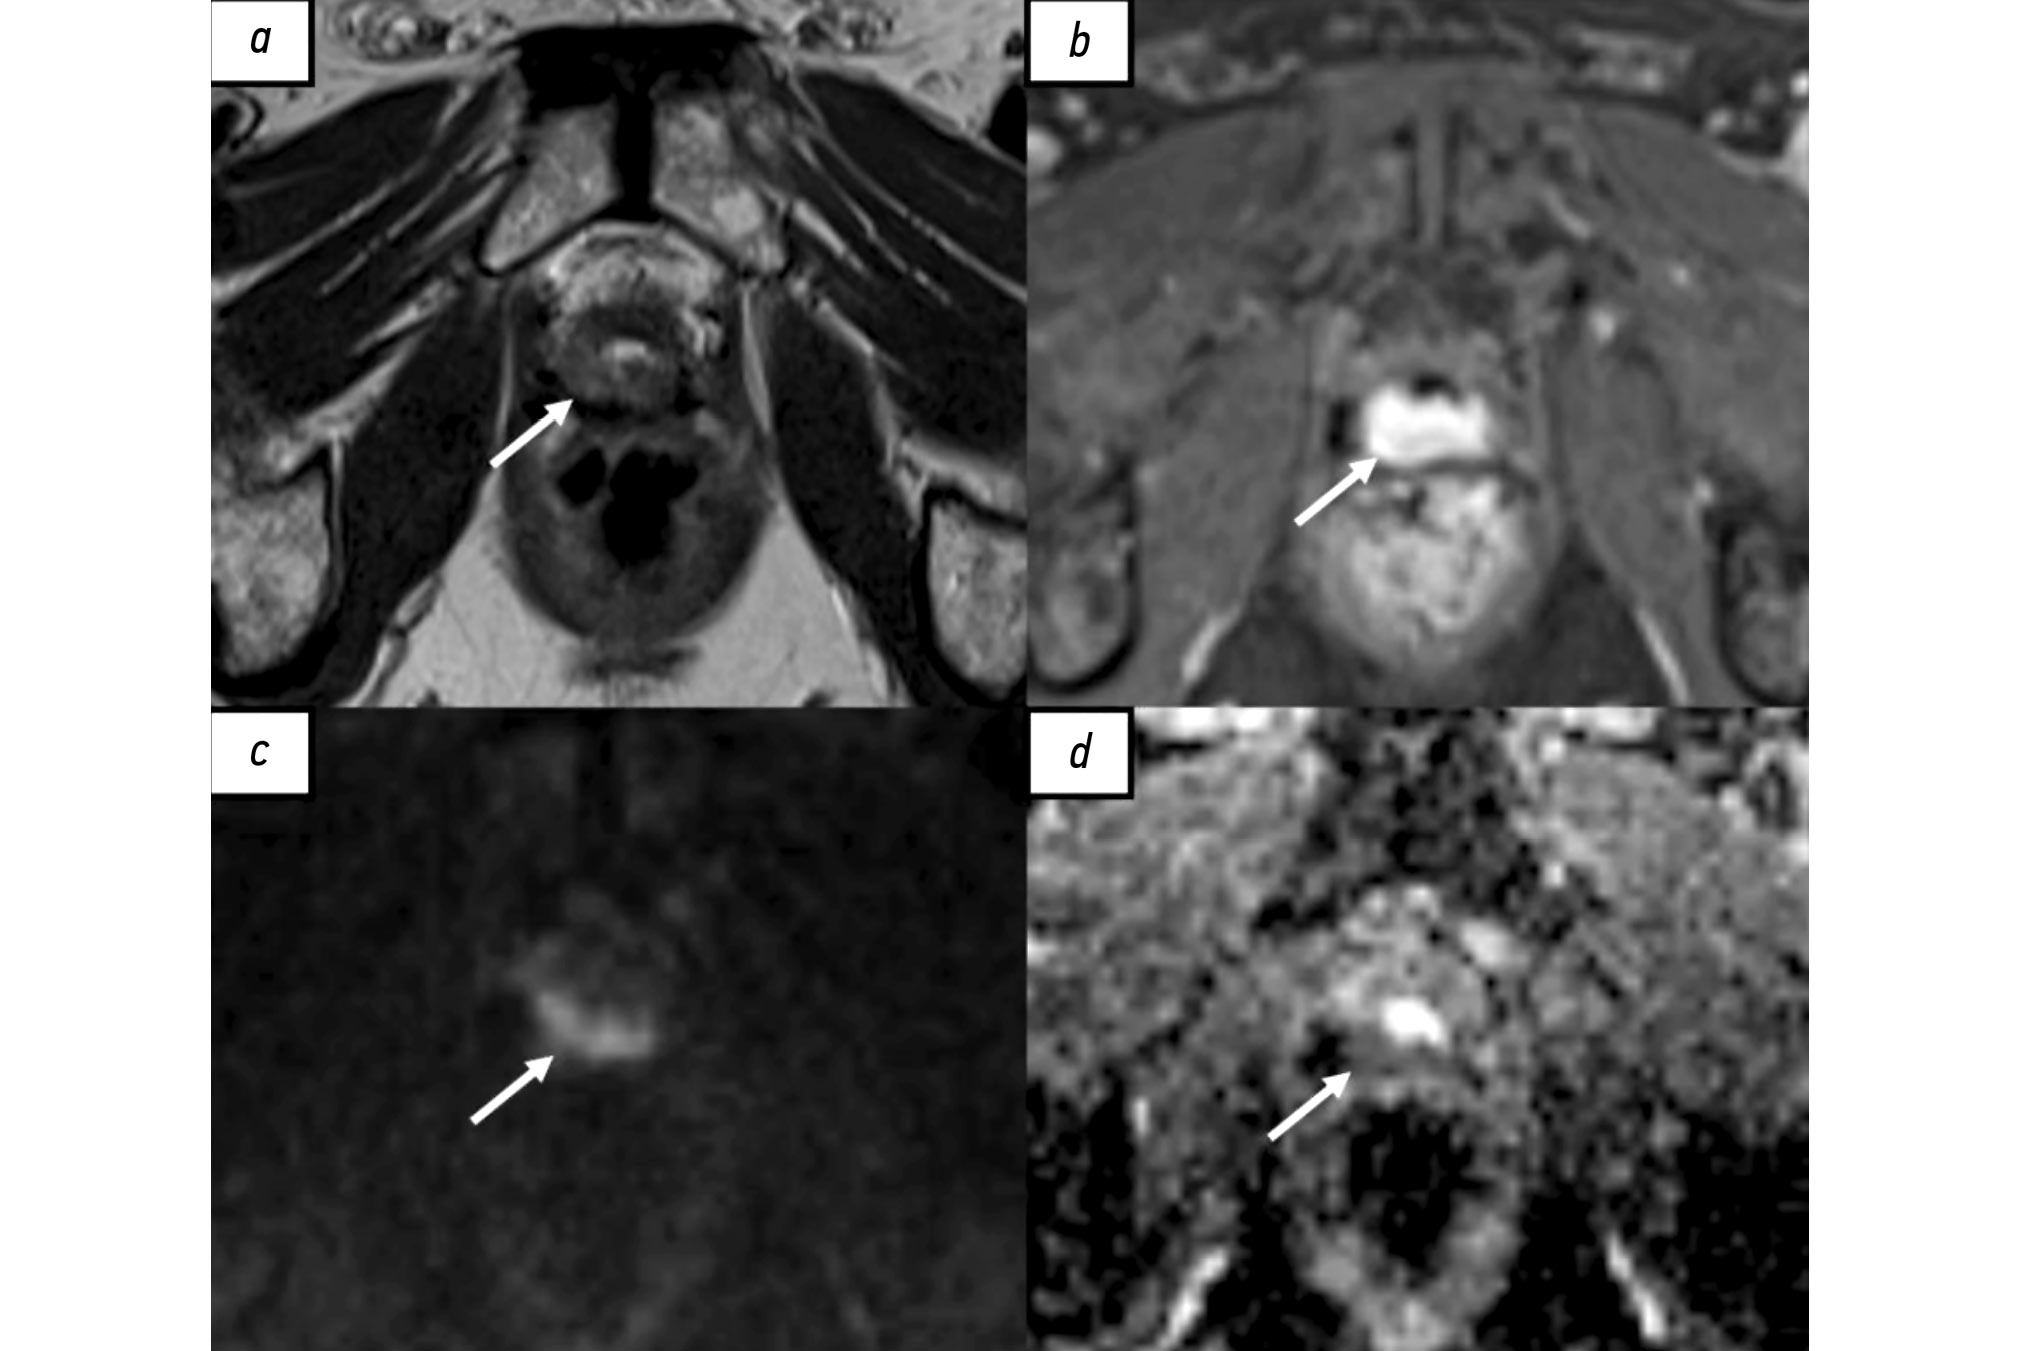

BACKGROUND: Prostate changes classified as PI-RADS 3 are a clinical situation requiring diagnostic accuracy and minimization of invasive procedures. Exploring the potential value of texture analysis in magnetic resonance imaging for prostate cancer risk stratification is critical in modern medical diagnostics.

AIM: To systematize and analyze current data on the application of texture analysis for prostate cancer risk stratification in patients with PI-RADS 3 and evaluate its diagnostic significance in differentiating clinically significant from clinically insignificant prostate cancer.

RESULTS: Analysis of the selected publications showed that machine learning and texture analysis significantly enhance the diagnostic accuracy of prostate cancer. These methods allow for more accurate risk stratification and determination of the actual need for biopsy, potentially leading to a reduction in unnecessary invasive procedures.

CONCLUSION: Texture analysis potentially enhances diagnostic accuracy in cases of prostate gland changes classified as PI-RADS 3. However, further research focused on standardizing techniques and conducting multicenter clinical trials is required for its widespread clinical application.